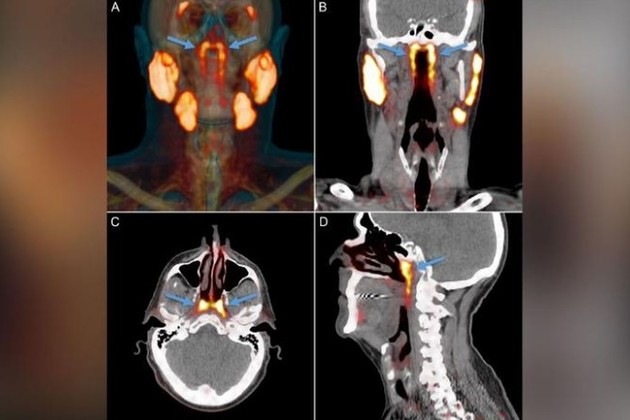

La «entidad desconocida» solo se identificó cuando los médicos utilizaban un tipo de exploración nuevo y avanzado llamado PSMA PET/CT que se ha utilizado para detectar la propagación del cáncer de próstata. PSMA PET es la abreviatura de la obtención de imágenes de antígeno de membrana específico de la próstata mediante tomografía por emisión de positrones. Las glándulas salivales se muestran claramente en este tipo de imagen altamente sensible . «Las personas tienen tres conjuntos de glándulas salivales grandes, pero no allí». Así dijo el autor del estudio Wouter Vogel, un oncólogo radioterapeuta del Instituto del Cáncer de los Países Bajos, en un comunicado de prensa en mayo.